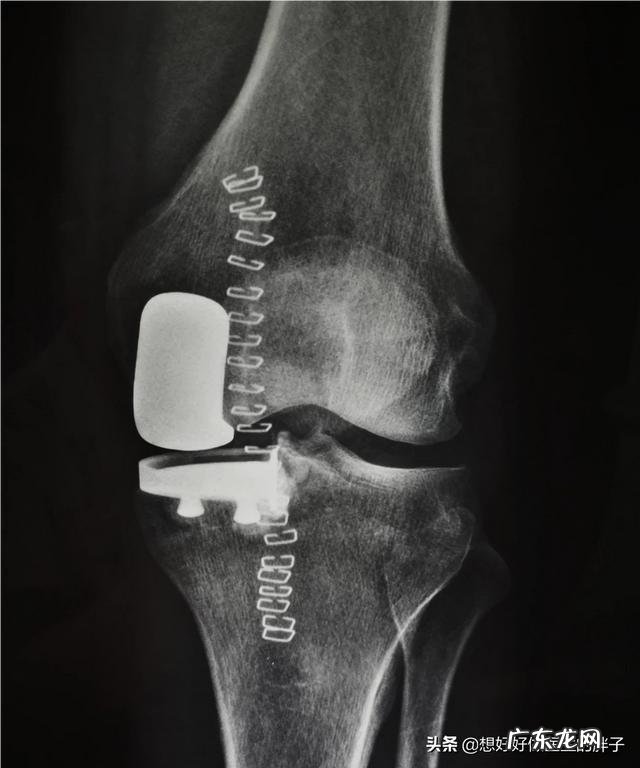

中期骨关节炎的zhi疗:患者到了中期,关节疼痛会有明显的加重,在坚持早期骨关节zhi疗的基础上,可以建议患者口服一些非甾体镇痛药,通常我们建议口服西乐葆这一类比较对胃黏膜伤害较轻的药物来控制疼痛 。也可以采取一些物理zhi疗的办法,比如微波zhi疗,超声波zhi疗,帮助控制关节炎症的进展 。由于中期骨关节炎患者的关节软骨已经有了明显的退变,部分患者的关节软骨会出现明显的皲裂与脱落,破碎 。那么此时,建议给关节内进行关节腔注射玻璃酸钠的办法来增加关节软骨的弹性,减轻关节软骨的摩擦 。

最近这几年,对于富血小板血浆因子也就是PRP的使用越来越广泛 。这是一种新的技术,可以采取患者自身的血液,经过专业的无菌技术给予离心出PRP,由于这种因子具有比较好的促进损伤修复的作用,最近也被开始用于关节腔注射 。